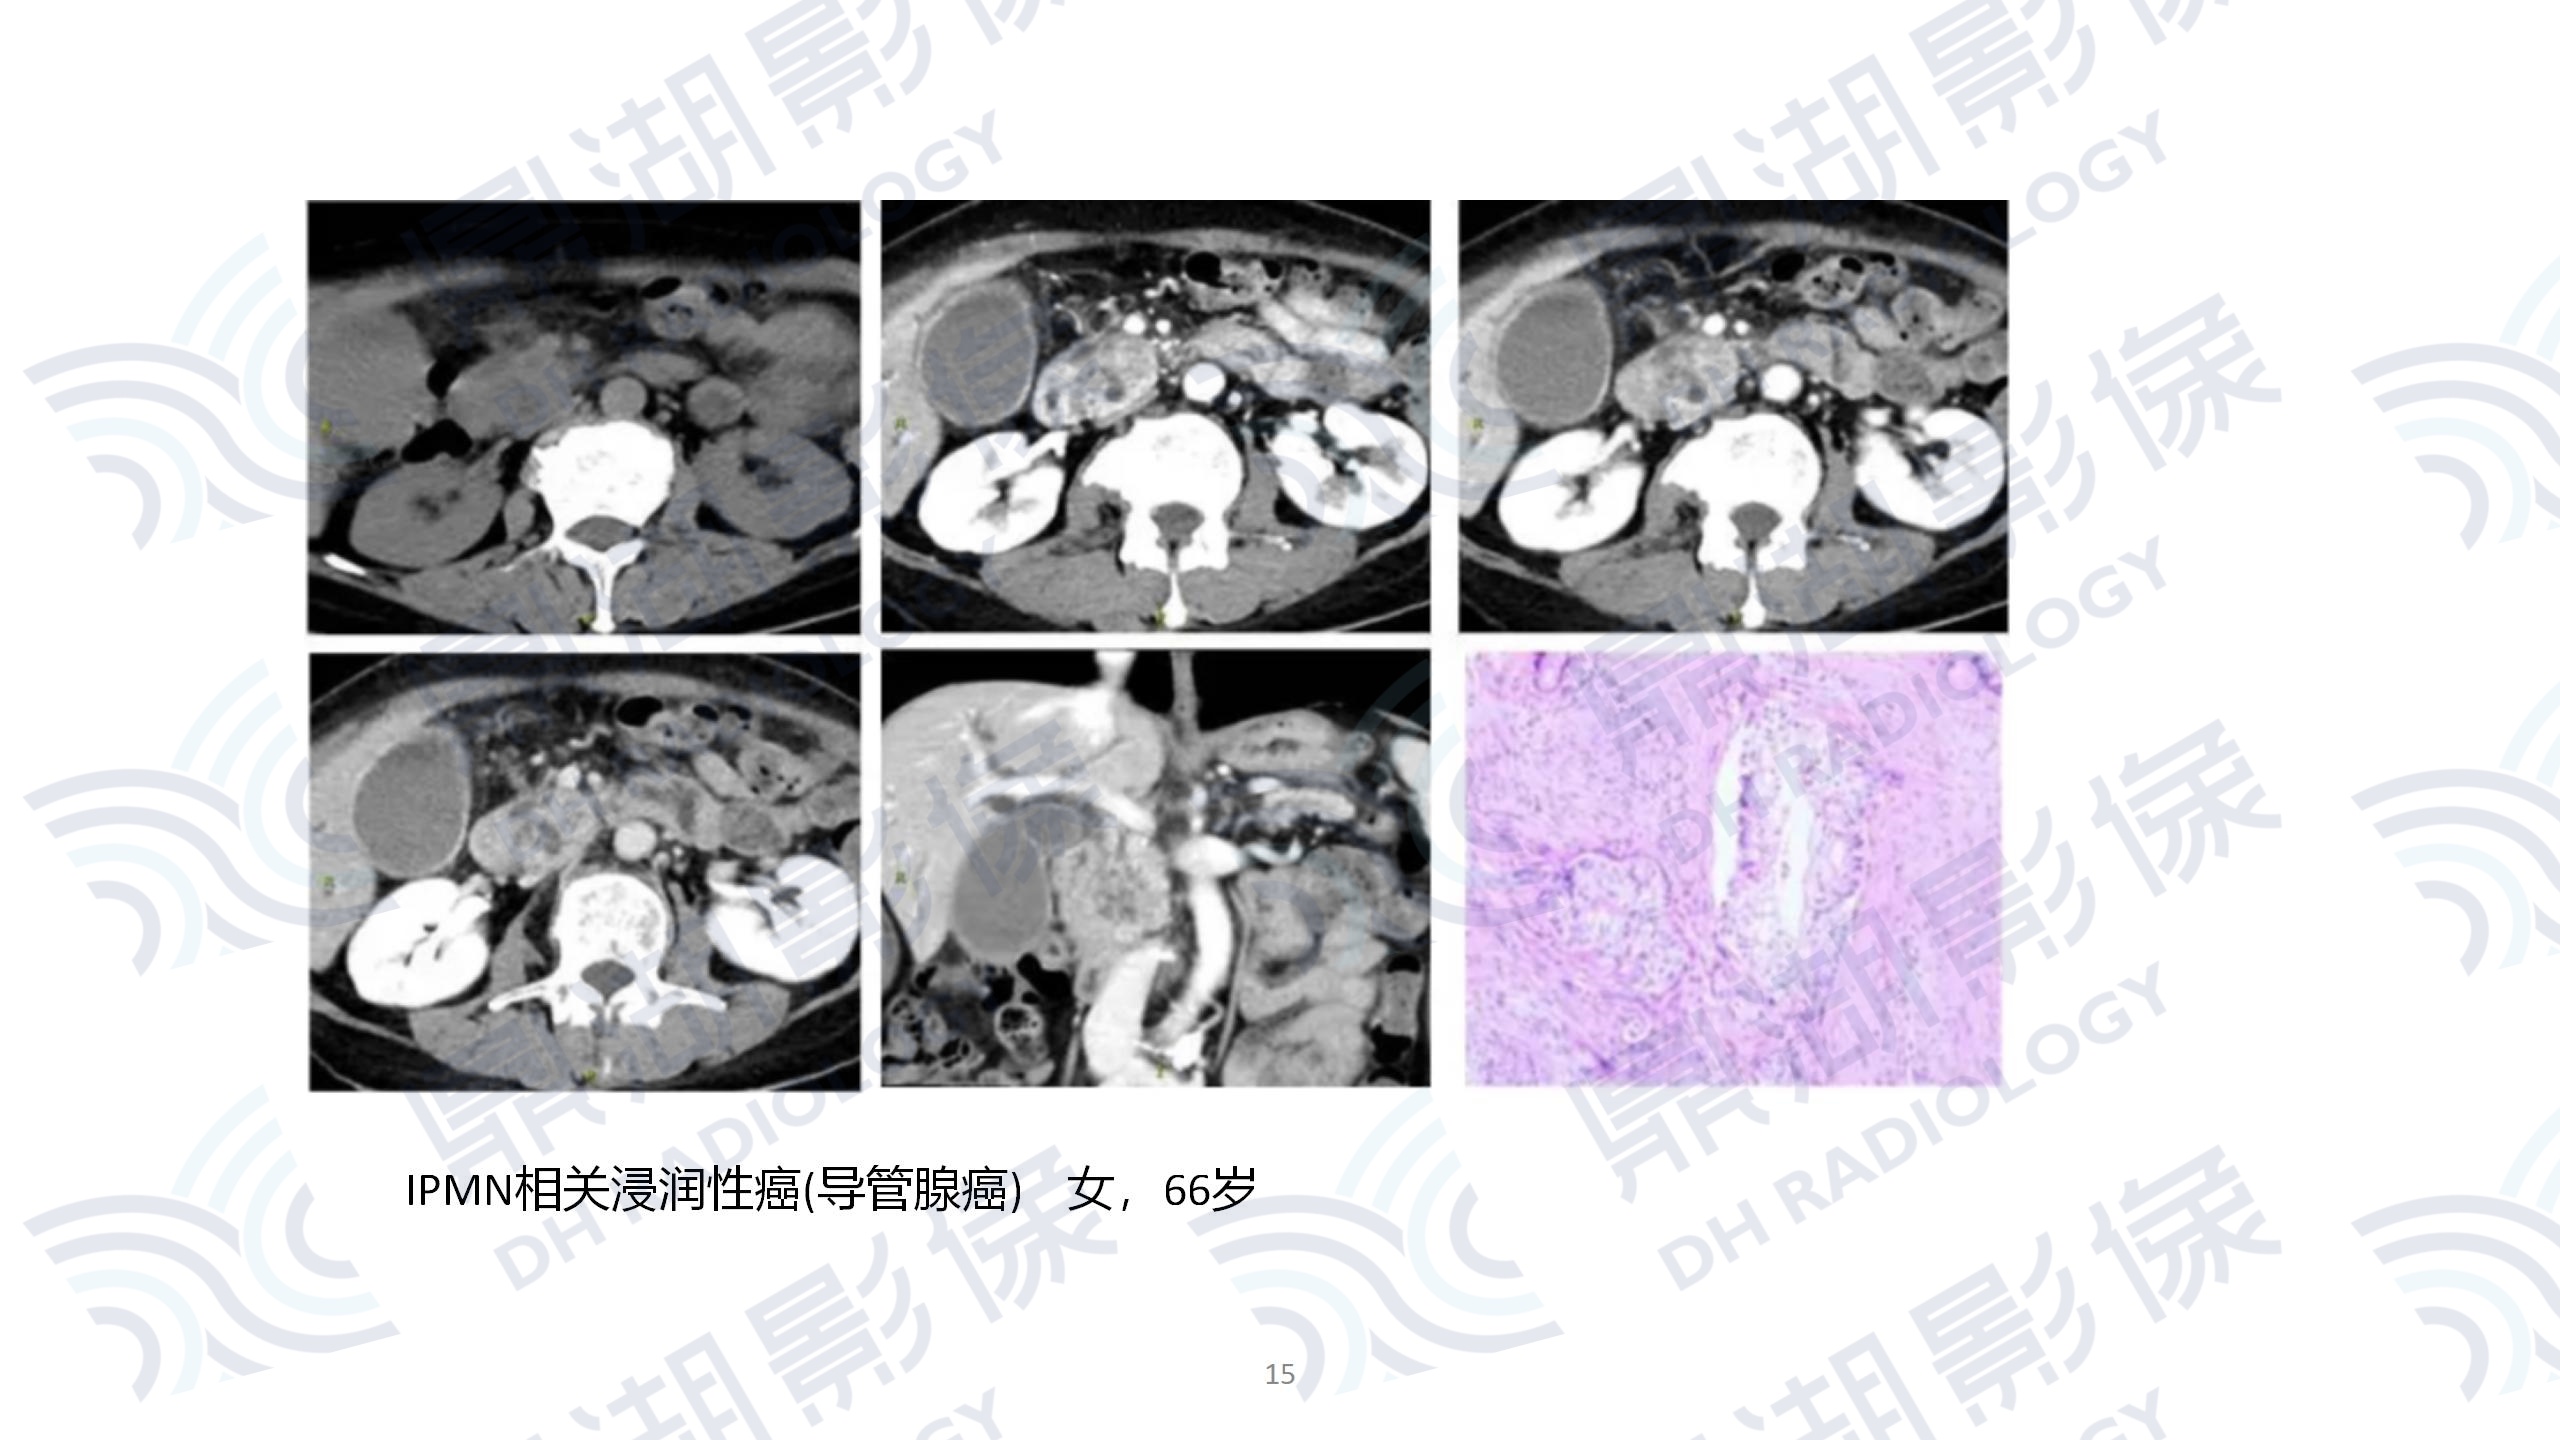

faf9bd7b569758137be2459a6d6358b2.jpg9dbb6dc40be4e83ac036465a293f7634.jpg64786b98144fd29747a02b3c3b25bf67.jpgbbeb9aad8dc251099799af04a61be571.jpg08bd065345df7d0d2b815b99938da241.jpgbd41e9d6233a178ffc615b3a9c18a2f1.jpg67d25d5fd4db7eaa226124eebb3d85e7.jpg2a6876b7d6716e60096536ed922ee8c1.jpg7f0255a99e57f71ee90d63f3df65a26f.jpga40f705b574187773a735d37963e700d.jpg0504c1d47a6ecf64a639652de1d7d87b.jpg66796921e3f062ccb333cff0d2d42926.jpg432be830c0c324773aa666d8c6db8df8.jpg3c3eade5ea39e2ebadca310ea8997056.jpg62971f2ae19dbdc6dbe418f7e93f9a66.jpg67a75fed3a589f8d51c41e3a432d1c3d.jpga3a7630d74a06bcd1367b7869c38e060.jpg85511e6307a90b305824ecc86c613c12.jpgde52548a6e0b62976f8c3c86d8608bfc.jpgf2cc8fe6db9171fef61134829e945a08.jpgfe97245386241567d65816ff04ec73a7.jpg945dad25a006f173fe10e443f4b41aaf.jpgdd8f01f0ad2cb7e9668e69d990962078.jpg